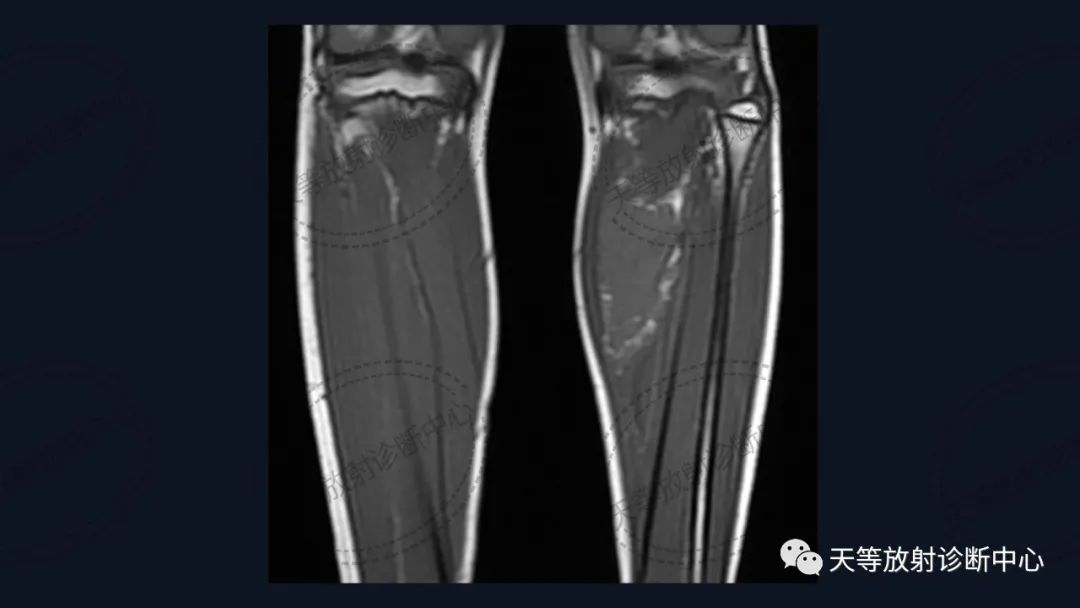

病例,儿童男性

前后两次对比观察,病灶略有增大。